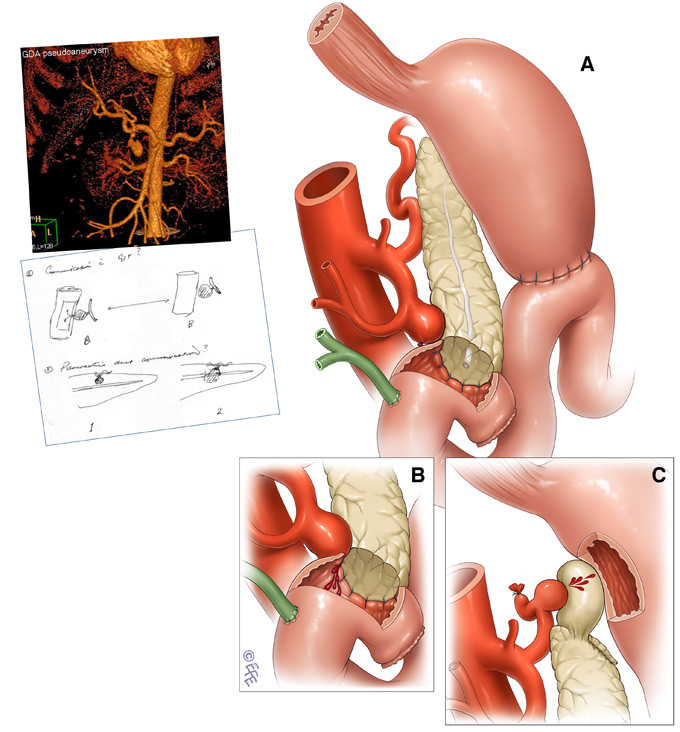

Фотографии медицинских исследований инсулиномы и синдрома Триады Уиппла